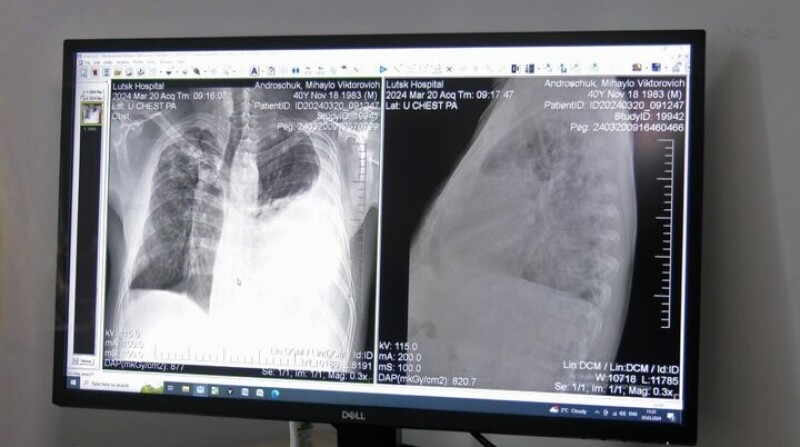

Щодня у рентген-кабінеті центру проходять обстеження орієнтовно 60 людей. Як зазначила завідувачка відділення Валентина Мостова, сюди направляють пацієнтів з підозрою на туберкульоз.

"Це туберкульоз в легенях і великий плеврит лівобічний ексудативний плеврит, тобто, набирається рідина в плевральній порожнині. Він до нас поступає на лікування, лікується і виписується майже здоровим", — сказала лікарка.